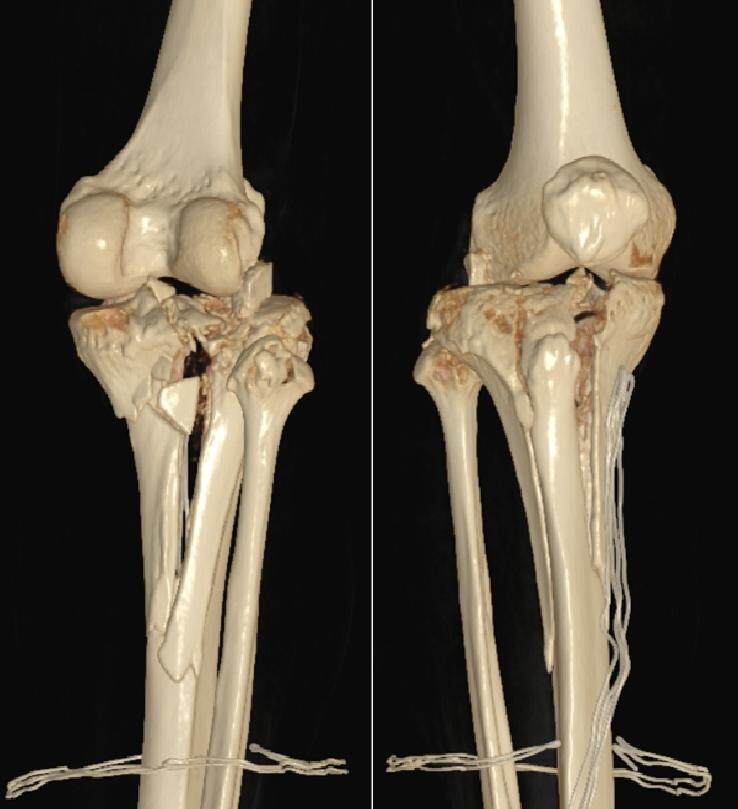

“这类骨折本身就非常复杂,像打碎的瓷器,想要复原难度非常大。”赵洪普教授解释,“从检查结果来看,王先生的胫骨平台呈爆裂性粉碎,关节面碎裂、塌陷严重,同时合并外侧半月板撕裂、内侧副韧带断裂。而且,患者本身有高血压,术中止血和术后感染防控都是很大的考验。我们的手术目标不仅是把骨头拼回去,更要最大限度恢复未来关节功能,避免创伤性关节炎,这对术者的技术水平要求非常高。”

手术团队通过精准设计的双侧L型切口,充分暴露“碎裂现场”,开始进行精细的“骨拼图”:先将碎裂、塌陷的关节面一块块翘起复位,用克氏针临时固定;接着,根据骨折块的部位和形态,巧妙选用T型钢板、L型钢板以及全螺纹加压空心螺钉进行组合式固定,为碎裂的骨骼搭建起稳固的“内部脚手架”;精细缝合了撕裂的半月板和内侧副韧带。C臂X光透视可见骨折复位良好,关节面平整。为防止感染并促进伤口愈合,手术还应用了封闭负压引流技术(VSD),并在术后用石膏托妥善固定。手术历时4个多小时顺利完成,出血控制良好。